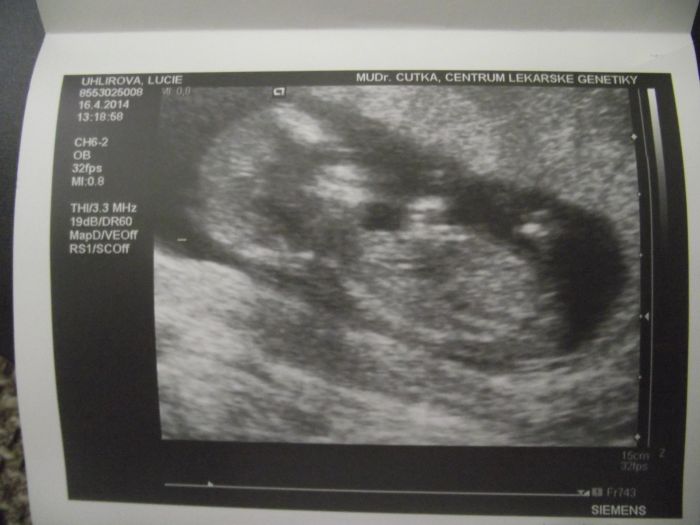

Autor: LuckaSt 16.4.2014 v 16:19

Tak už jsem zpět ze screeningu:-).. Vše v pořádku, bylo to hrozně rychlý.. A i když by si přítel moc přál chlapečka a i mi dnes vyšel v tom čínským kalendáři, tak to vypadá na 85% na holčičku

.. Je mi to líto kvůli chlapovi, ale co, hlavně že je zdravá .. A podle pm jsem dnes 11+6 a podle ultrazvuku dokonce 13+4, naměřil 7 cm, což teda čumím, protože v pondělí pan doktor naměřil 6cm.. Takže snad to nejhorší je za mnou a teď už si budu jen užívat těhulkování :-)

[517841]

Luci, týýý jo, to je fotečka!!!!! Tak moc moc moc gratuluju!!!!!!! Holky, mě to vždycky tak zahřeje, když tu napíšete, že je to v pořádku

Lucko,tak gratuluju,krásné miminečko. To už je krásně velký, nádherná fotečka. Já si těhu naštěstí užívám od začátku,jelikož mi není skoro vůbec špatně, jen občas mě navečer trápí žaludek, jinak je vše ok.

Holky dík, no vážně koukal mezi ty nožky a říkal.. No.. Moc tam toho teda nemá.. Tak na 80-85% to bude holčička, ale že mi to potvrdí v tom 20tým týdnu. Tak holky co už byly měli většinou mimi do 6cm, tak třeba ten cenťák dělá s přirozením hodně :-).. Jako malinká naděje na kluka je, ale myslím, že už je to konečná :-)

Luci gratuluji krásná fotečka a že ste zdravý